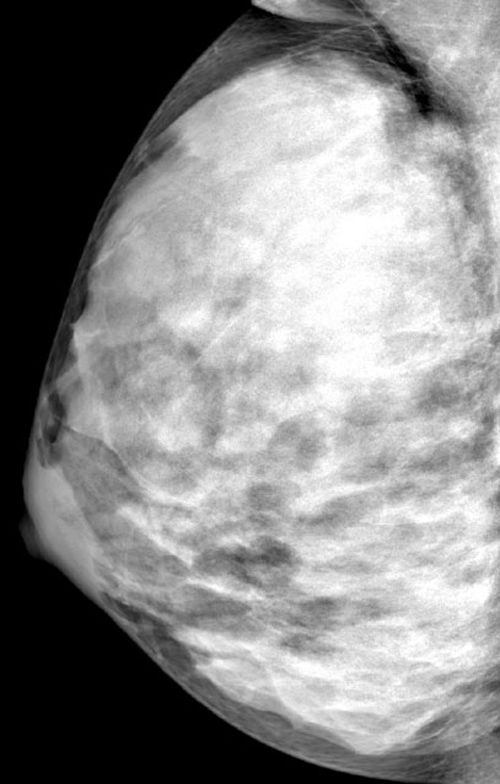

What’s your diagnosis?